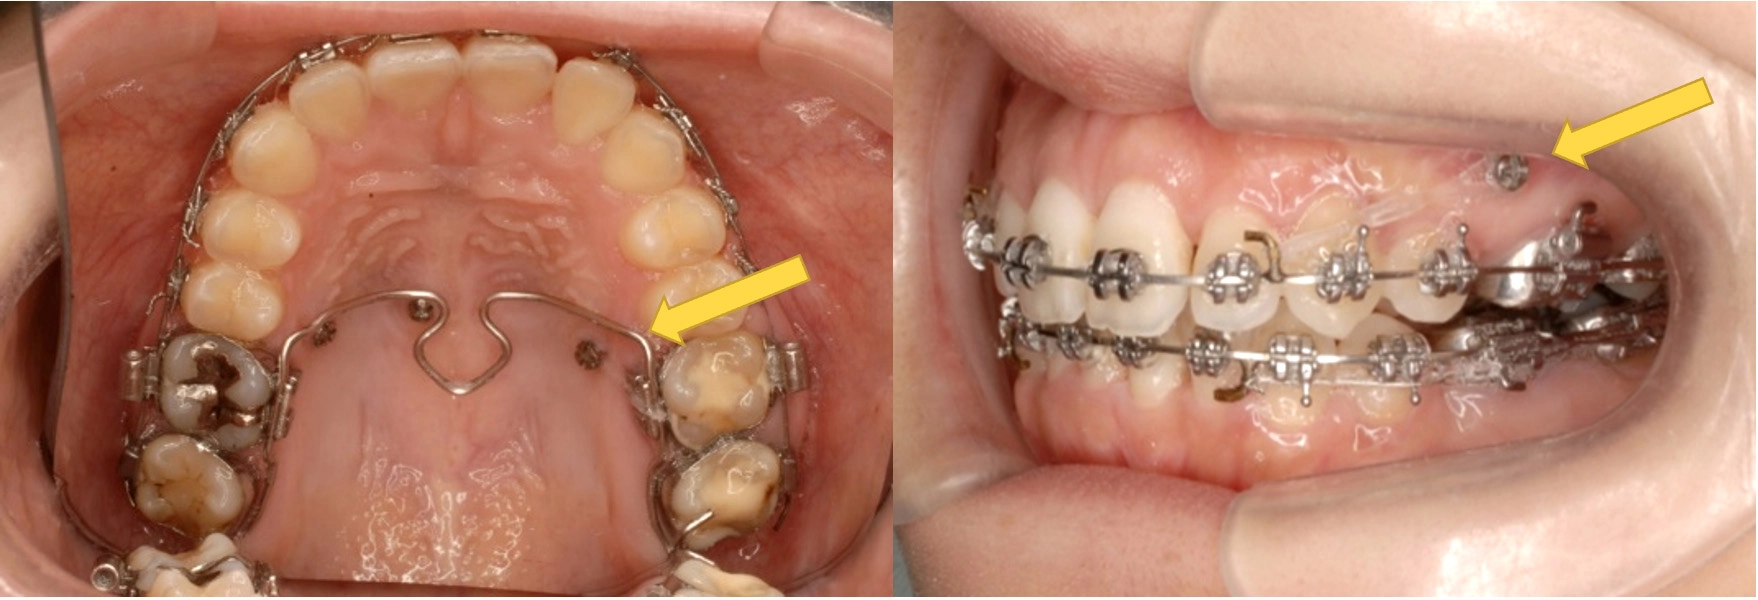

歯の根っこの向き(黄色の矢印)や、骨との位置関係を精密にシミュレーション。根元からの移動を計画します。